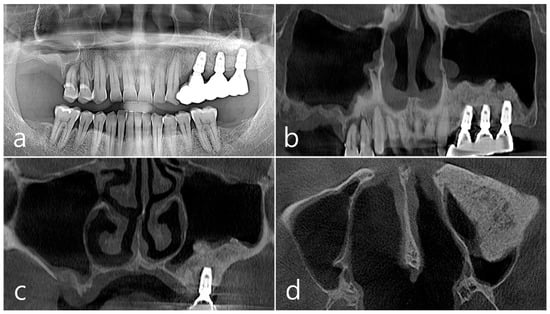

This patient, a 67-year-old female non-smoker, reported no systemic disease that could interfere with the operation. The patient visited the clinic for implant placement for the missing teeth. Panoramic radiography and CBCT were taken. On panoramic radiography, resorption of residual alveolar ridge and pneumatization of the maxillary sinus were observed in the left and right posterior region. Since the amount of residual alveolar bone was 4–6 mm in the maxillary right posterior region, a transcrestal sinus lift was planned (Figure 1a). In the preoperative panoramic, coronal, and axial images of the CBCT scan, abnormal images of the maxillary sinus were not observed, and there was no sinus membrane thickening (Figure 1b–d).

Figure 1. Case 1. (a) In panoramic radiography, resorption of residual alveolar ridge and pneumatization of the maxillary sinus were observed in the left and right maxillary posterior region; (bd) In preoperative CBCT’s panoramic, coronal, and axial images, there were no abnormal findings of the maxillary sinus and no sinus membrane thickening.